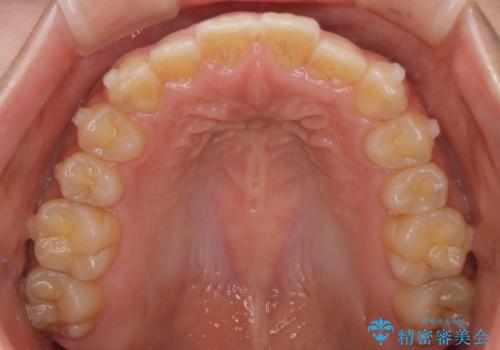

- 前歯の叢生を主訴に来院されました。非抜歯でインビザラインで治療をしました。

叢生はIPRをし、並べました。この患者様はオープンバイトだったため歯を並べる過程でかみ合わせも治しました。